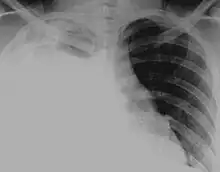

Hydrothorax is the synonym of pleural effusion in which fluid accumulates in the pleural cavity. This condition is most likely to develop secondary to congestive heart failure, following an increase in hydrostatic pressure within the lungs. More rarely, hydrothorax can develop in 10% of patients with ascites which is called hepatic hydrothorax. It is often difficult to manage in end-stage liver failure and often fails to respond to therapy.

Pleural effusions may also develop following the accumulation of other fluids within the pleural cavity; if the fluid is blood it is known as hemothorax (as in major chest injuries), if the fluid is pus it is known as pyothorax (resulting from chest infections), and if the fluid is lymph it is known as chylothorax (resulting from rupture of the thoracic duct).